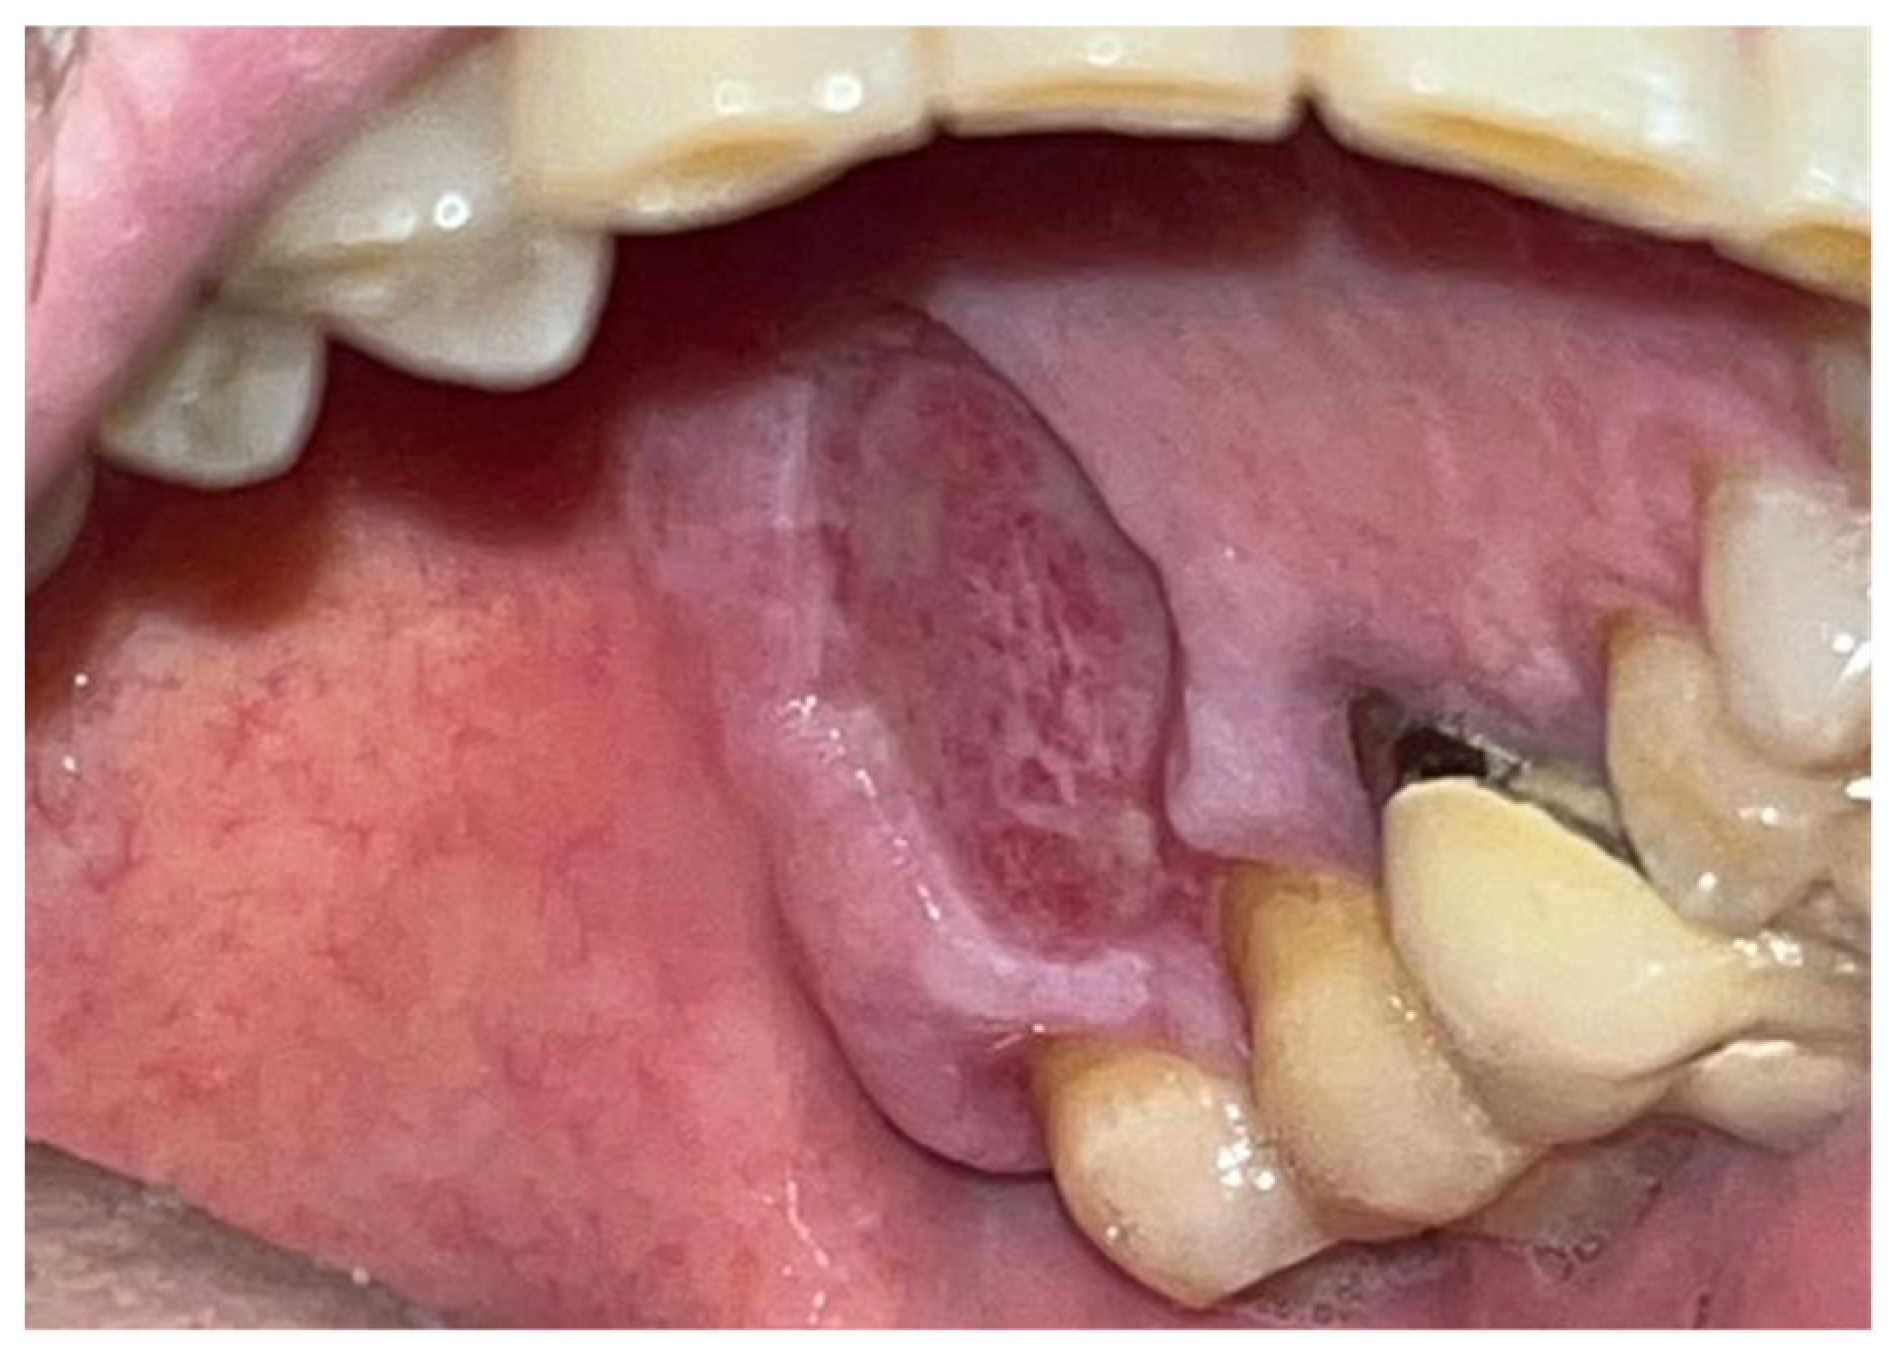

The study involved nine patients diagnosed with cardiovascular conditions, selected according to clearly defined inclusion criteria: presence of diagnosed cardiac conditions, the need for oral surgery, and signed informed consent. Exclusion criteria included patients with known allergies to the components of Glubran II, active infections, or systemic conditions contraindicating surgery. All patients were administered an antibiotic regimen consisting of Amoxicillin + Clavulanic Acid (875/125 mg), GlaxoSmithKlin, London, UK starting 24 h prior to the procedure, which was performed after obtaining cardiology clearance. Excellent results in terms of managing intra- and postoperative bleeding and tissue healing were observed in a 67-year-old patient with hypertension and diabetes mellitus, who underwent an excisional biopsy of a white lesion located on the palate with a leukoplakic appearance. The lesion, located on the palatal vault, appeared white, non-glossy, with undefined margins and soft consistency, and was non-removable via scraping biopsy (Figure 1 and Figure 2). A decision was made to surgically remove the lesion with wide incision margins to provide a biopsy sample (containing the lesion with surrounding healthy tissue) to the Department of Pathological Anatomy at the University Hospital of Rome Tor Vergata.

The patient was prepared for the surgical procedure with antibiotic therapy (Amoxicillin + Clavulanic Acid 875/125 mg) and 2% Chlorhexidine rinses starting the day before the surgery. Following the guidelines for patients with hypertension (Figure 1), the excision was performed with the complete removal of the lesion, adhering to standard surgical procedure techniques (Figure 3). Post-excision, hemostasis was achieved using Glubran II surgical glue. In this case, an endodontic needle was used for material application, allowing single droplets to be applied directly to the surgical site (Figure 4). Hemostasis was rapidly achieved in the areas where the glue was applied. The material was carefully deposited around the perimeter of the surgical site, ensuring individual droplets were placed without excessive application (Figure 5).

This technique resulted in optimal hemostasis within seconds, creating a stable, chemically and mechanically secure film protecting the surgical site during the healing period. The patient was re-evaluated 2 weeks post-surgery and reported no discomfort from the glue application, describing the film as hard but not interfering with any essential functions. Over the following two weeks, the film progressively degraded until it was eliminated. The degradation of the film allowed for the formation of new, mature epithelial tissue at the surgical site, with no signs of inflammation or suppuration in the surrounding tissues, though traces of Glubran II remained within the lesion site (Figure 6).

Figure 1. Lesion resembling leukoplakia localized on the palate, non-removable through biopsy by scraping.

Figure 2. Leukoplakia-like lesion localized on the palate following scraping with a sterile gauze.